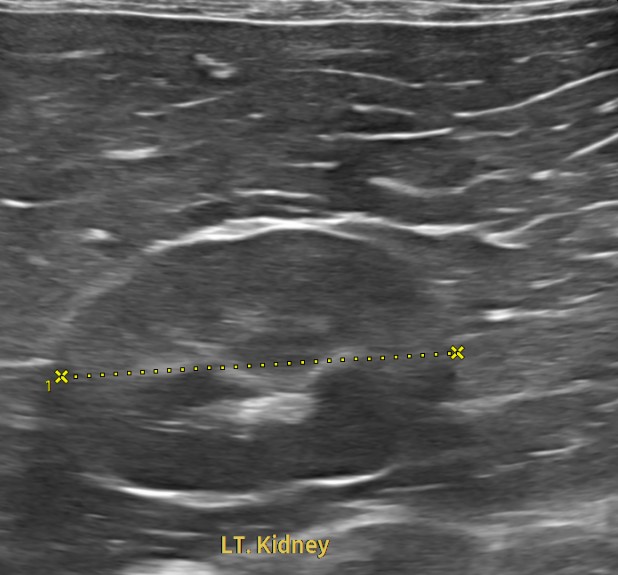

이번 아이처럼 특별한 증상을 보이지 않는 경우라도, 혈액검사·초음파·흉부 및 복부 영상검사 등을 한 번에 묶어 진행하면 현재 장기 기능을 객관적으로 확인하고, 잠재적인 질환의 방향성까지 파악할 수 있습니다.

혈액검사에서는 주요 장기 수치, 염증 수치, 전해질 균형 등을 확인했고, X-ray는 흉부·복부 전반의 장기 구조를 점검했습니다. 초음파는 장기 실질 구조나 미세한 이상까지 확인할 수 있어 검진의 핵심 항목으로 포함됩니다. 치과검사는 일반적으로 마취가 동반되어, 구강전용 엑스레이 촬영을 해야 정확한 판단이 가능하지만 치과전문 병원인 만큼 육안으로 기본적인 검사는 해드리고 있습니다.